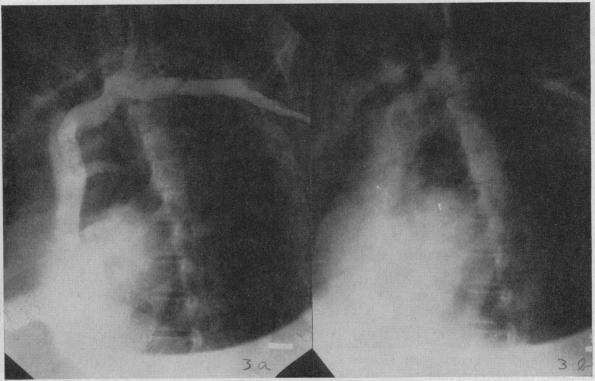

Angiocardiography is indicated in selected cases of heart disease in which a definite diagnosis cannot be made by ordinary methods or in which there is reasonable expectation that the information so obtained may influence the treatment of the patient. Whenever possible, angiocardiography should be done in conjunction with cardiac catheterization. The main indication for angiocardiography is cyanotic congenital heart disease; primarily those cases in which there is a right-to-left shunt. Angiocardiography is occasionally of value in diagnosis of other types of congenital heart disease and in acquired heart disease.